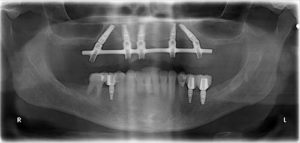

All on 4 Case 1

Before

After after all on 4 x-ray view female patient case 1

Male

Dr. Cavaretta